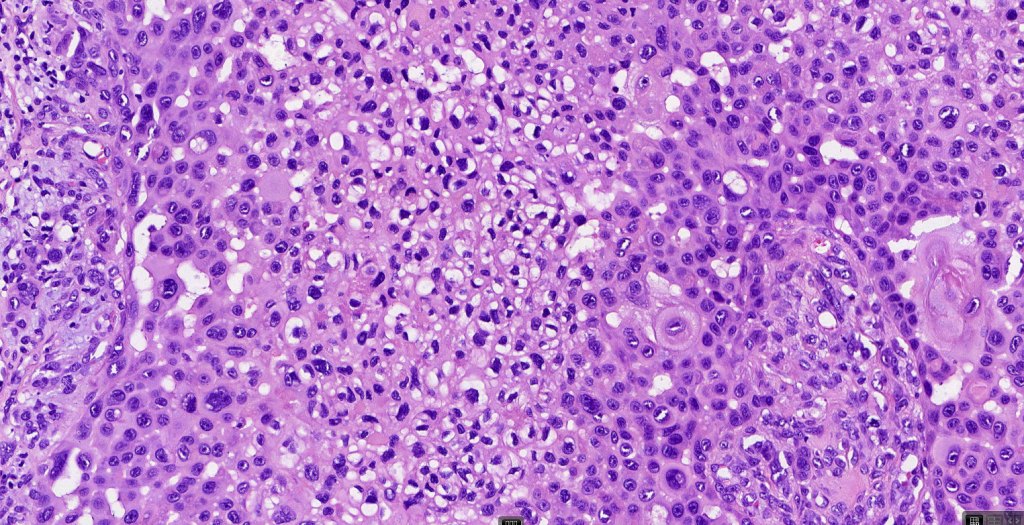

•Biphasic tumor combining squamous cell carcinoma and adenocarcinoma; the latter showing ductal and glandular differentiation

•Glands are lined by cuboidal to columnar epithelium

•Glandular foci show mucin

•Variable pleomorphism & mitotic activity but can be marked

For comparison an actholytic squamous cell carcinoma- in cases of doubt, IHC and special stains for mucin will resolve the problem.